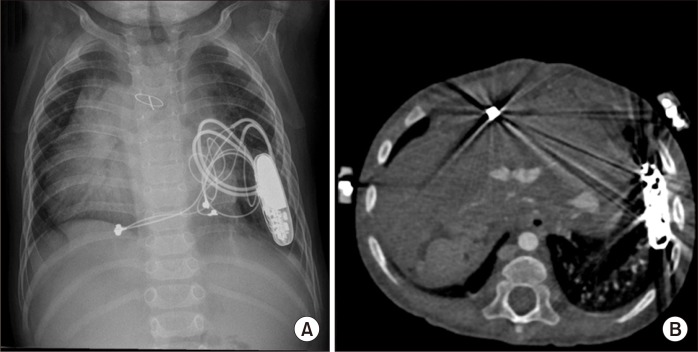

A Case Report of Rare Complications after Epicardial Permanent Pacemaker Implantation in an Infant: Airway Compression, Skin Necrosis, and Bowel Perforation.

Insertion of an epicardial pacemaker is a useful treatment for pediatric patients with an abnormal heart rhythm. However, there are limitations and concerns when implanting epicardial pacemakers in infants and neonates due to their small body size. We report a patient who experienced rare complications after implantation of a permanent pacemaker.